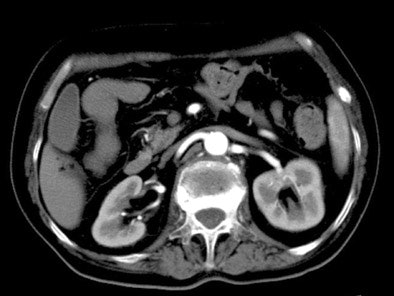

| Above, 5-second delay (renal arterial phase) 73-year-old female patient. All images courtesy of Dr. Hironori Nishibori and Dr. Masa Kanematsu. |